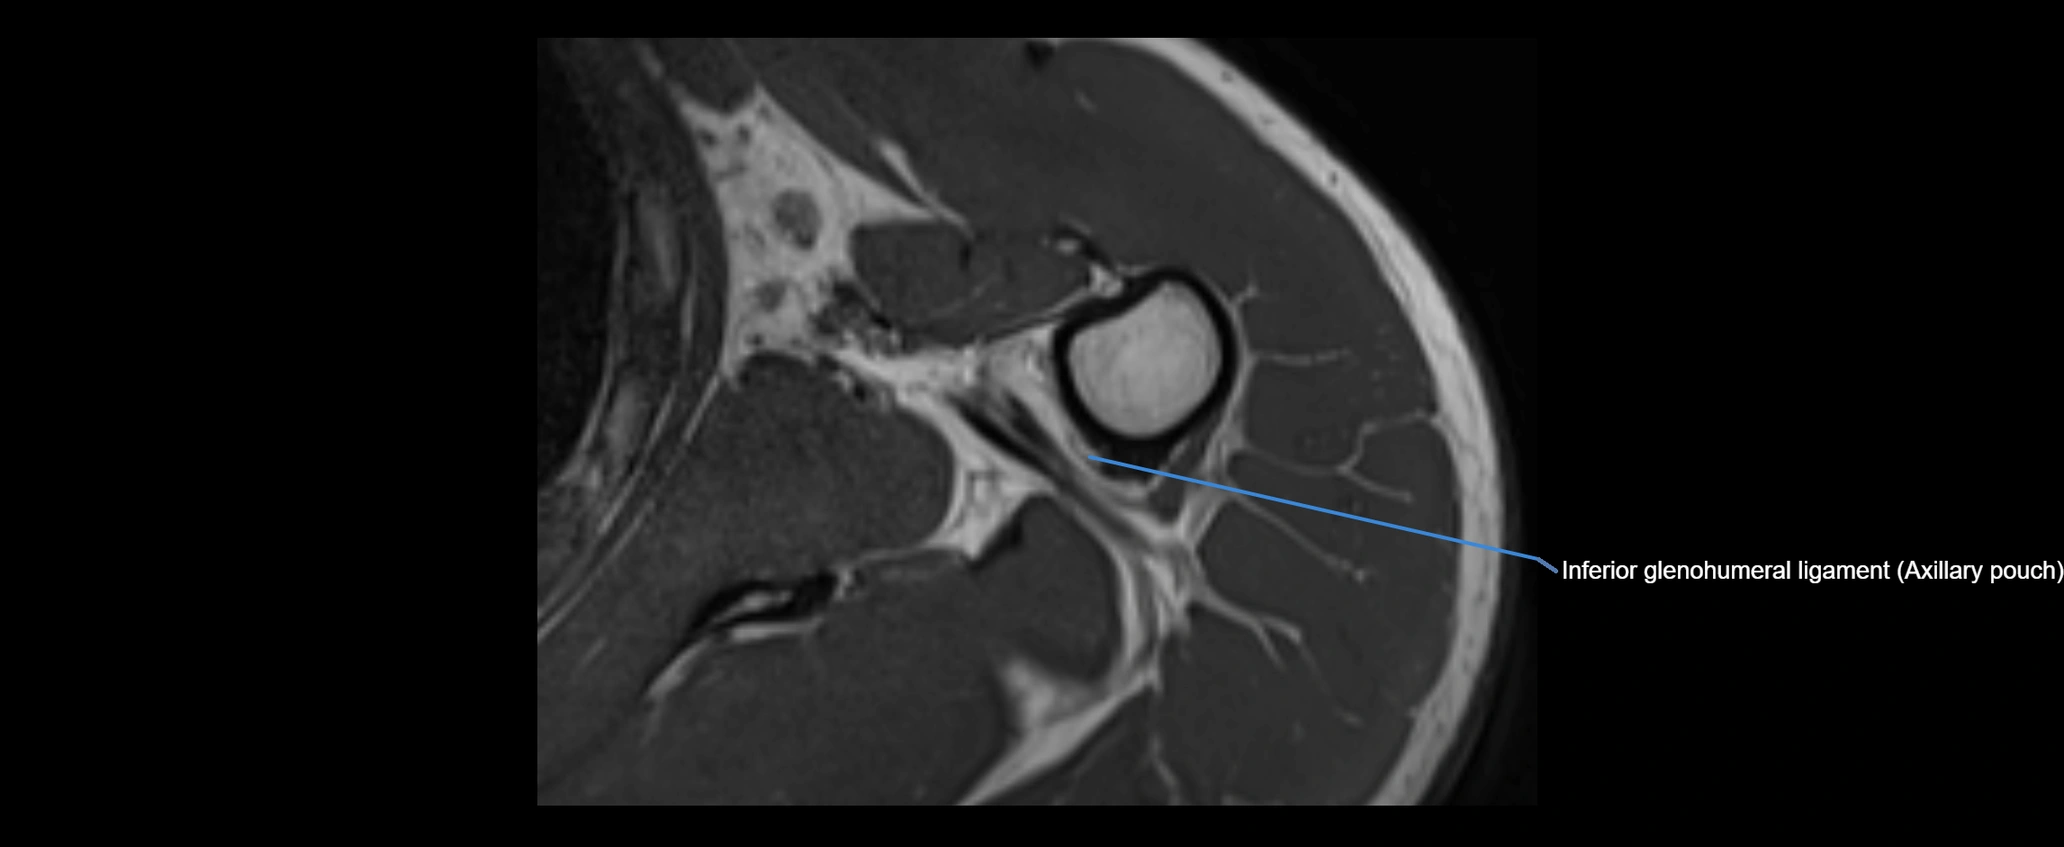

MRI Appearance

• T2-weighted images:

• Normal ligament: Low signal, homogeneous.

• Partial tear or sprain: Focal hyperintensity or thickening.

• Complete tear: Discontinuity with fluid-bright gap between clavicle and acromion.

• Associated edema: Bright signal in distal clavicle or acromion marrow.

• Proton Density Fat-Saturated (PD FS):

• Normal ligament: Low signal, uniform thickness.

• Partial tear or sprain: Bright signal or contour irregularity.

• Complete tear: Clear discontinuity with bright signal gap and joint effusion.

• Excellent for assessing joint capsule, coracoclavicular ligaments, and periarticular edema.

MRI images

image